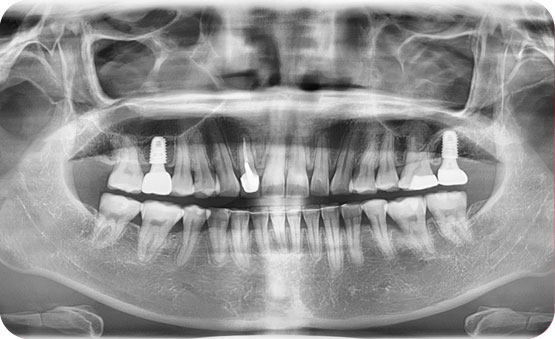

하악 구치부 손실 부위의 사랑니 견인으로 배열

Before

After